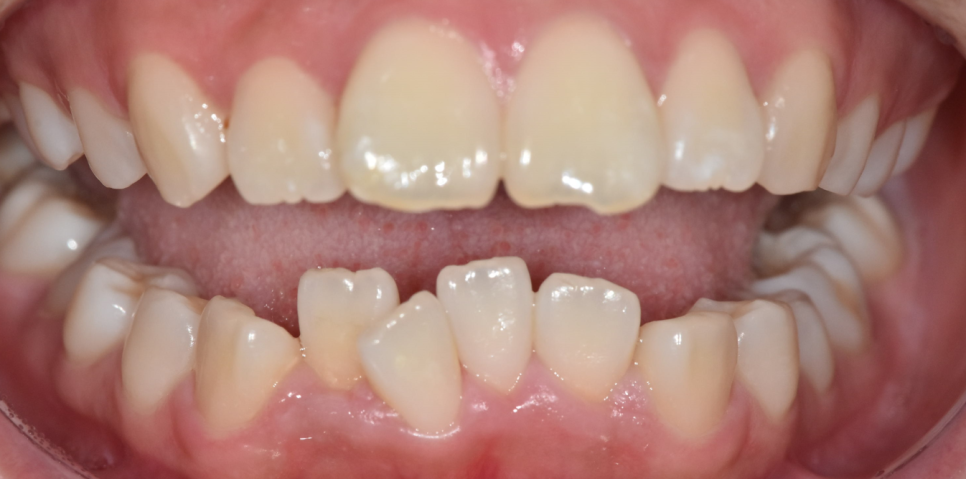

교합 상태, 치아 배열 상태를 확인하기 위해

5분할 포토라 불리는 구강 내 사진을 찍고

뽄도 뜹니다.